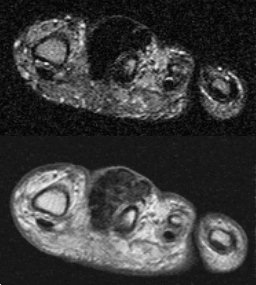

Case 5 (Menu)

gctts1.jpg (17017 bytes)gctts2.jpg (16162 bytes)